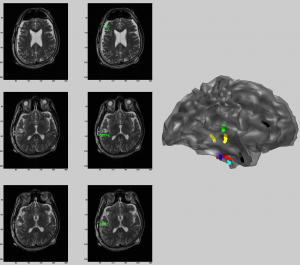

Project Summary: Epilepsy is one of the most  common diseases related to the disfunctioning of the central nervous system. For the patients whose drug therapy turns out to be ineffective, it is a common method to identify the locations of sources that trigger the seizure in the brain tissue and resect them through surgical means for treatment. When the surgical therapy is to be applied, seizure history, physical and neurological inspections, radiological imaging data (MRI, CT, PET), neuropsychological tests, psychiatric inspections and long term video and EEG monitoring data are evaluated by an expert group of neurosurgeons and neurologists. It requires to locate the epileptic focus using the EEG data recorded from the surface as well as from the deep sites located in the brain in order to improve the  widely  accepted current surgical planning approach. It is critically important to identify the  source locations of seizure activity for the epileptic surgery. This undoubtedly provides  a very important information to the clinical team for the surgical planning. The major aim of this study is to perform source localization using the surface and deep electrode EEG data obtained from epileptic patients and hence, to provide a biomedical support to the surgical planning. As a result, by applying a smaller number of electrodes it is aimed to offer less inconvenience to the patient as well as to reduce significantly the cost and duration of the surgical procedure.

Keywords: EEG source localization, epilepsy, deep/subdural electrode